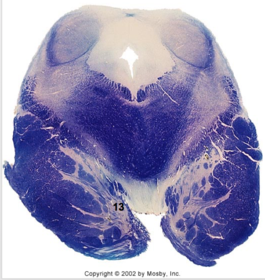

| Longitudinal pontine fibers (corticospinal tract) | |

| Transverse pontine fibers (dark fibers) | |

| Pontine nuclei (pale) | |

| Medial lemniscus | |

| ALS | |

| Trapezoid body | |

| Ventral trigeminothalamic tract | |

| Superior olive | |

| Central tegmental tract | |

| Facial nerve root fibers - descending | |

| Facial motor nucleus | |

| Interposed nuclei | |

| Medial longitudinal fasciculus | |

| Facial nerve root - internal genu | |

| Abducens nucleus | |

| Lateral vestibular nucleus | |

| Superior vestibular nucleus | |

| Inferior cerebellar peduncle | |

| Superior cerebellar peduncle | |

| Dentate nucleus | |

| Fastigial nucleus | |

| Anterior spinocerebellar tract | |

| Spinal nucleus of V | |

| Spinal tract of V | |

| Middle cerebellar peduncle | |